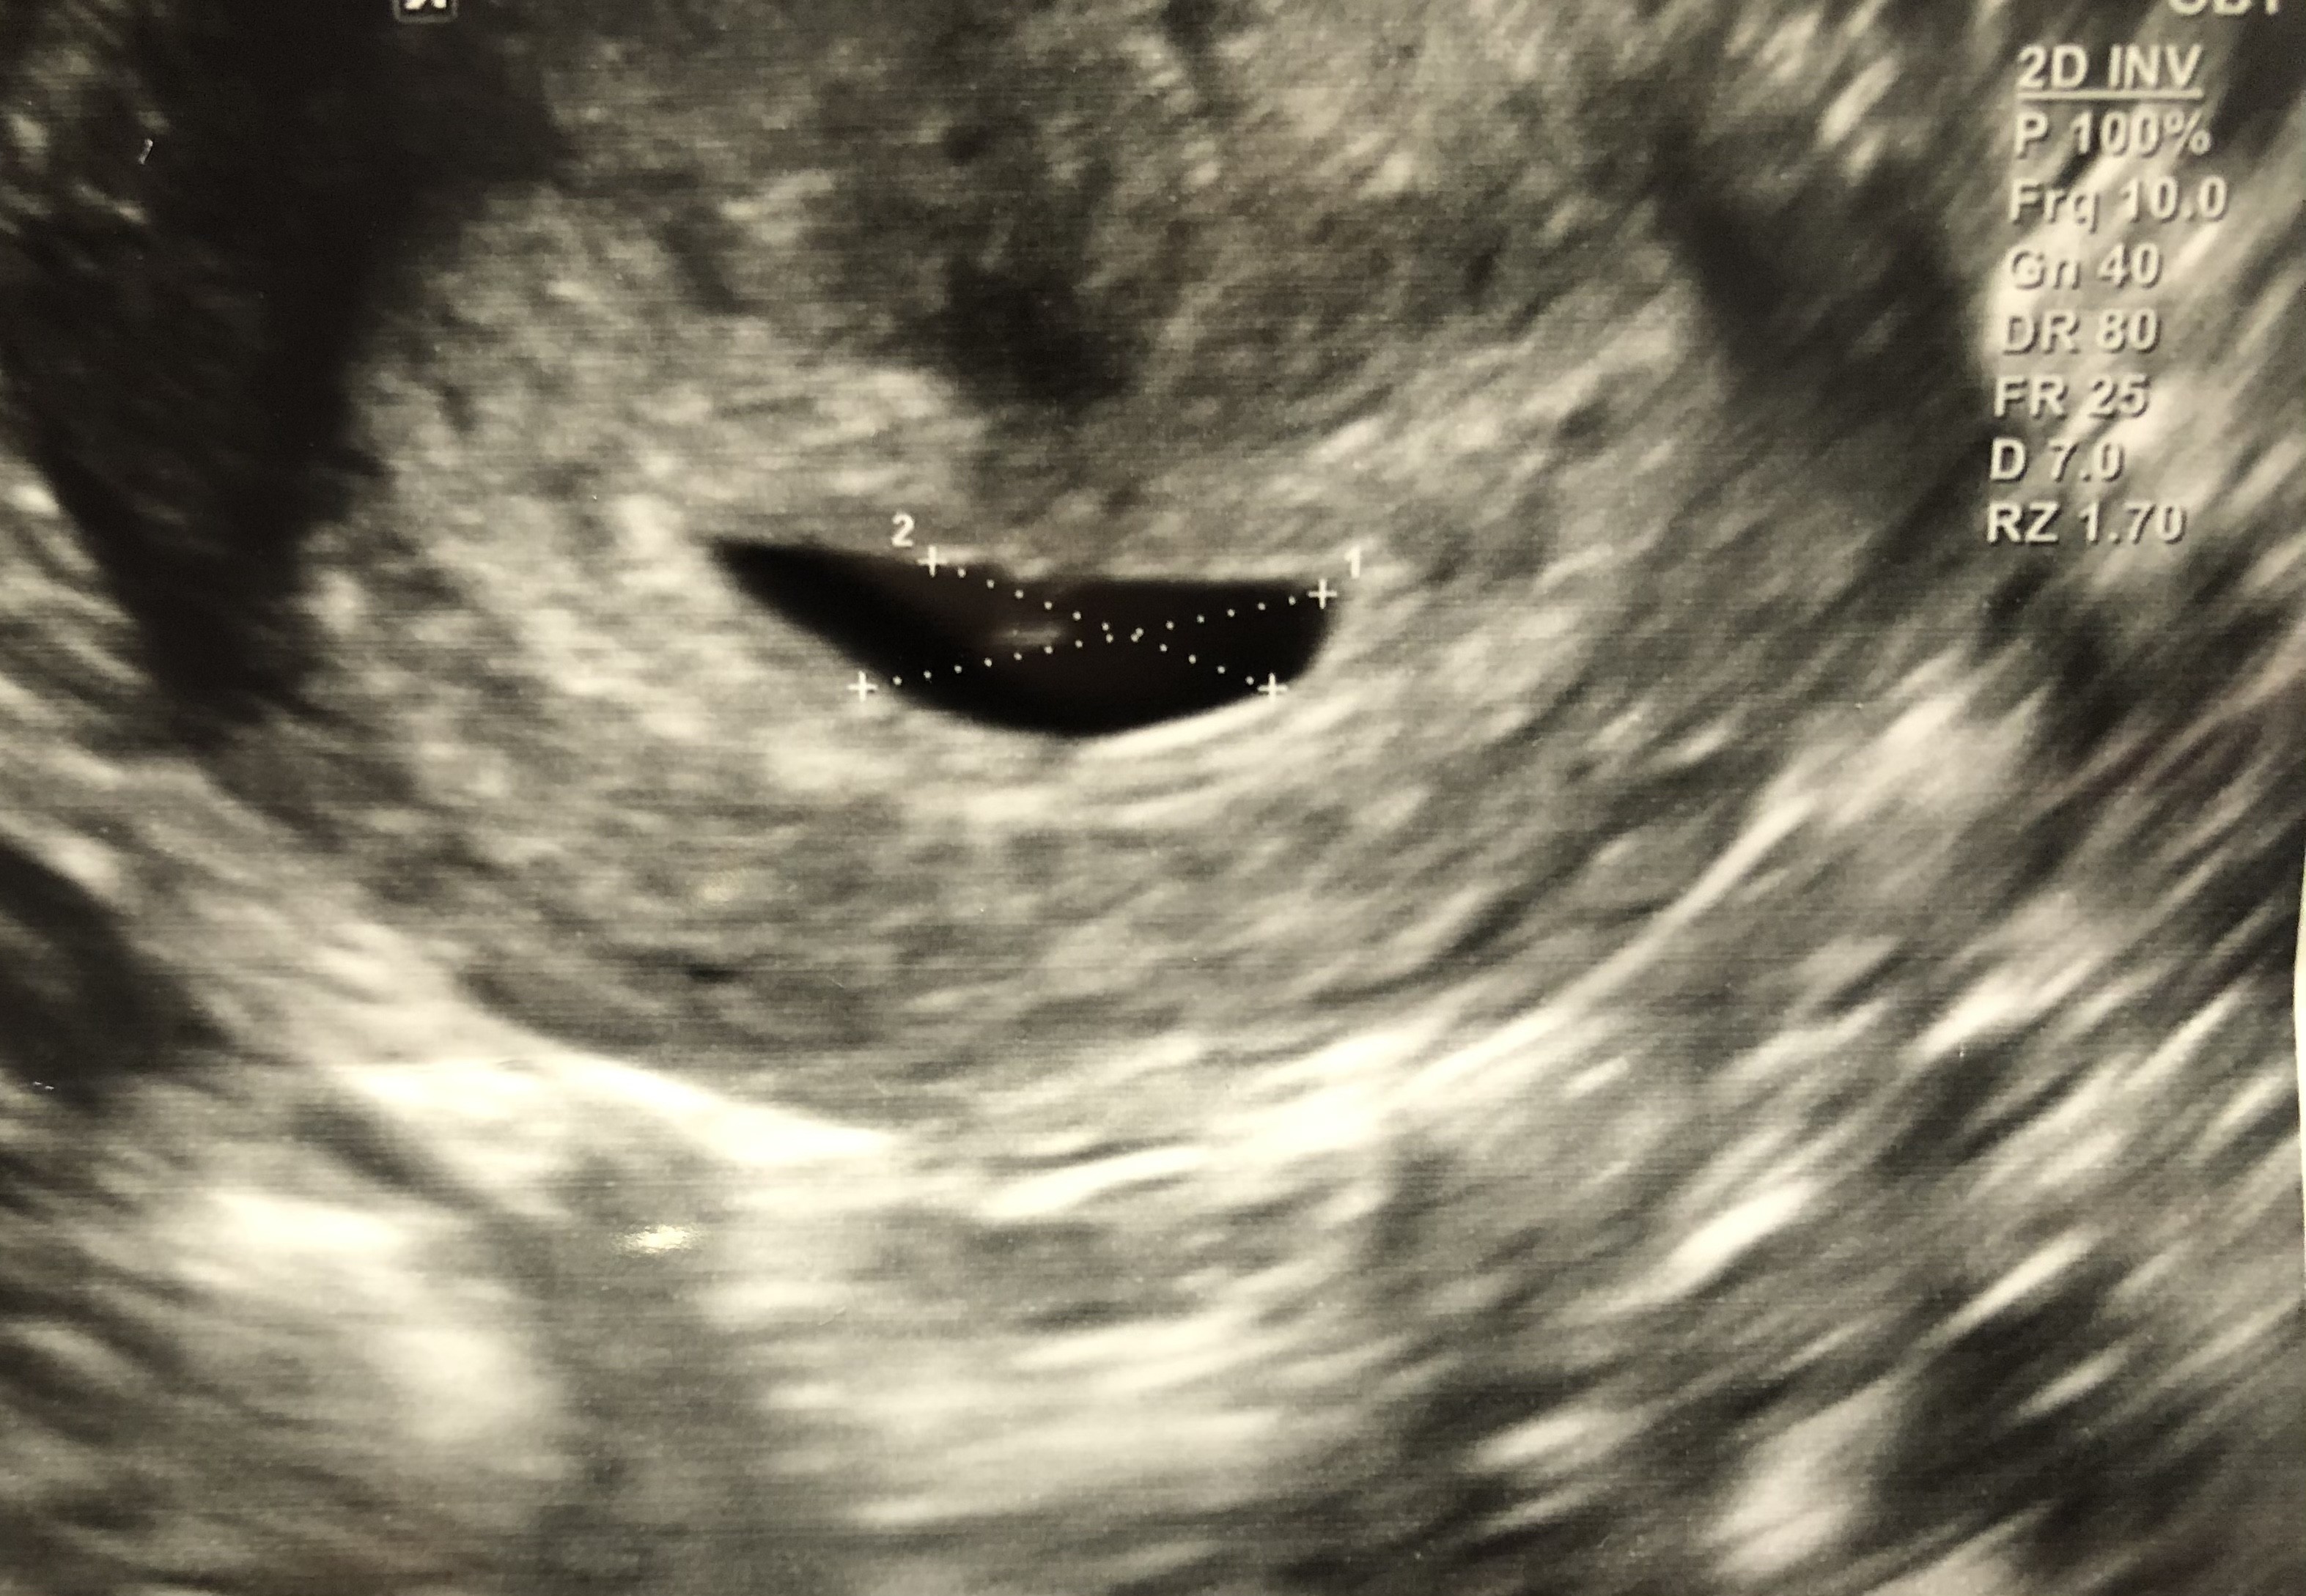

Zaczelam się bardzo martwić po wczorajszej wizycie 😭 przecież w tym moim pęcherzyku prawie nic nie widać, a to już 5+5... 😭 i na dodatek lekarz mi zapisał duphaston, w sumie nie wiem czy te mała plamka to zarodek, czy pęcherzyk żółtkowy... byłam tak zestresowana ta wizyta, ze mało co zakodowałam 😳 dołączę jesscze raz zdjęcie, może któraś z Was się wypowie?

• 625FC925-5757-490D-ABA7-7B324139E63C.jpeg

625FC925-5757-490D-ABA7-7B324139E63C.jpeg

1,1 MB · Wyświetleń: 101